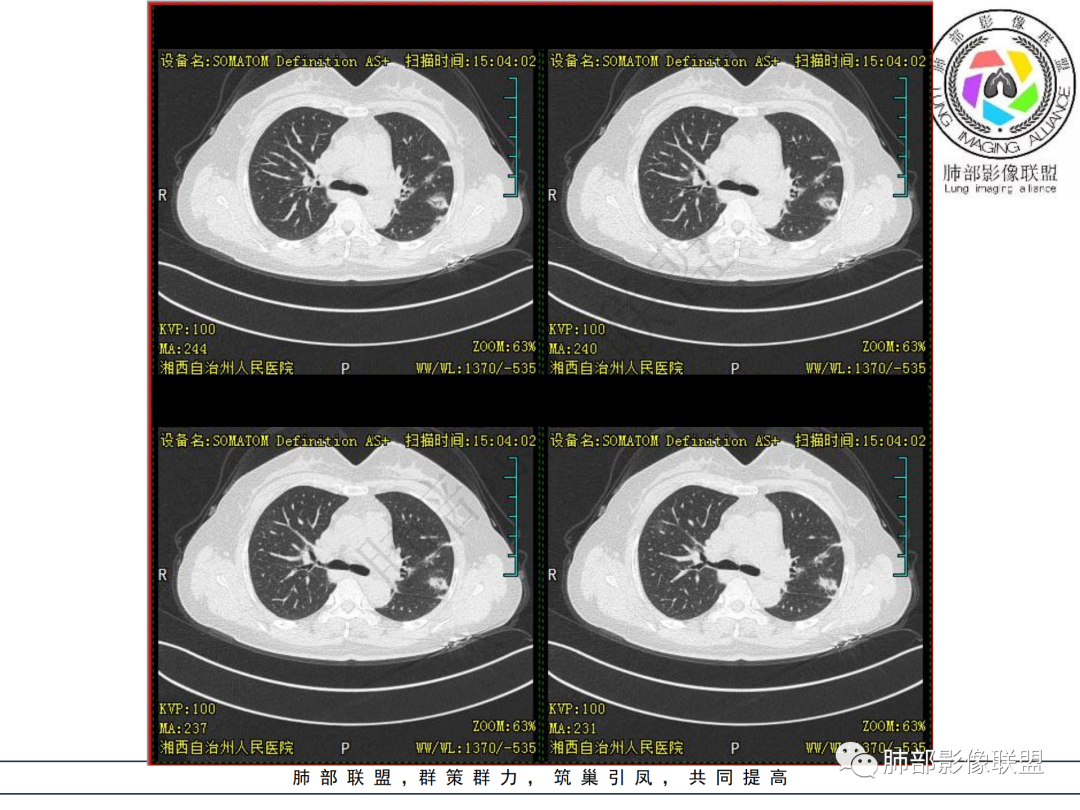

胸部CT提示双肺多发的斑片实变结节影,磨玻璃。病灶分布以双肺胸膜下为主,部分病灶以支气管血管素分布,病灶内可见支气管穿行。总体符合间质性肺疾病。

考虑间质性肺疾病,机化性肺炎,

中年女性,类风关,无发热及呼吸道症状,类风湿因子升高,双肺多发斑片影、结节影,胸膜下分布为主,部分沿支气管血管束分布,CTD-ILD,机化性肺炎可能

中年女性,类风湿病史,无发热咳嗽,炎性指标不高,类风湿指标高。影像 :双肺多发结片状、结节状稍高密度影,双肺外周分布为主,延支气管血管束分布,大部分病灶边缘平直,部分病灶内网状改变,有病灶跨叶,支气管血管束增粗,肺动脉高压,考虑类风湿结节,机化性肺炎,鉴别肉芽肿性血管炎,